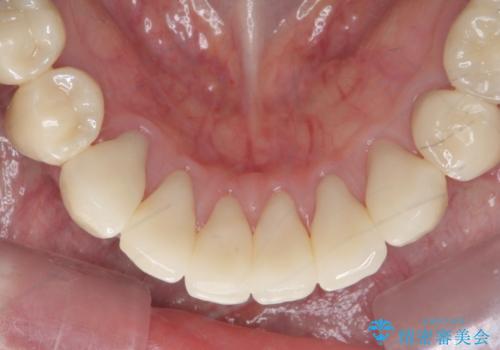

シェーグレン症候群で多発した虫歯 前歯のセラミック治療

- シェーグレン症候群は唾液の分泌が減少し、ドライマウスなど口腔内の乾燥症状が出る疾患です。

唾液分泌が減少すると、虫歯になりやすく、小さな虫歯にコンポジットレジンを充填を繰り返した結果 写真のような継ぎ接ぎだらけの歯になってしまいます。

充填されていたコンポジットレジン・小さな虫歯を丁寧に全て取り除いたのち、歯全体を覆い虫歯の再発予防を期待できるセラミッククラウンで補綴を行います。

- 66万円(仮歯・ジルコニアクラウン×6)費用は治療当時の料金となります

コンポジットレジン修復は小さな虫歯を除去したのちの充填には向きますが、充填箇所が複数になってくると審美障害や虫歯の再発リスクが高まります。